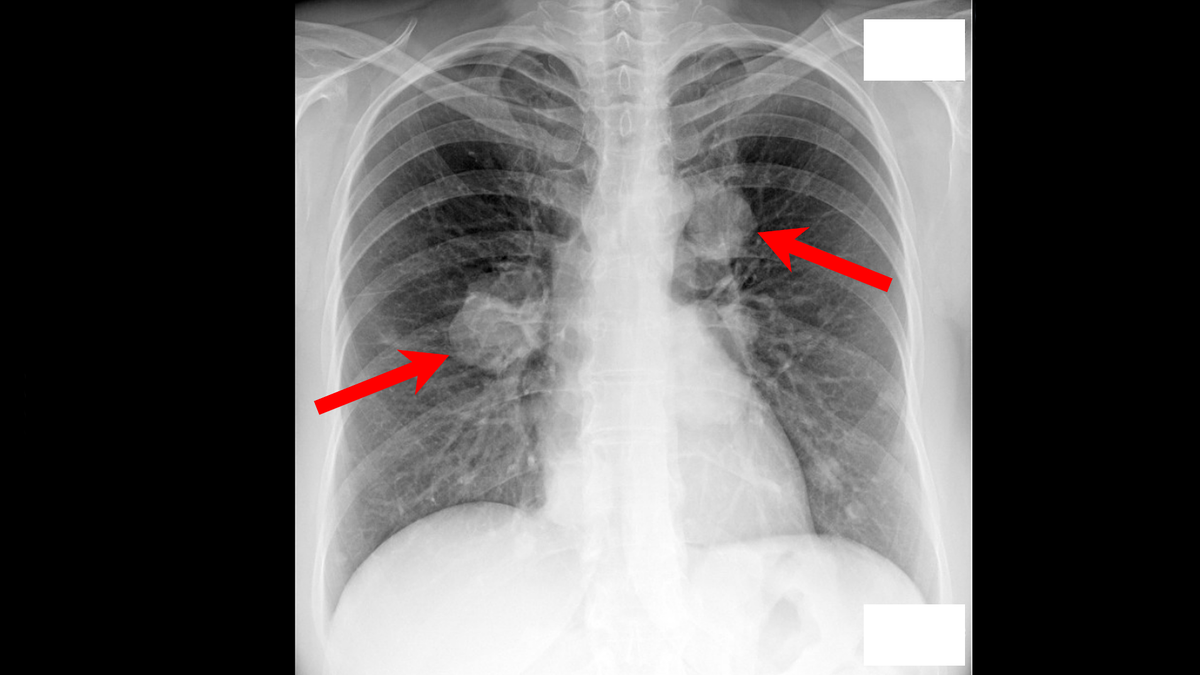

Начало истории было в октябре 2024 года, в момент очередной диспансеризации, когда флюорография неожиданно показала наличие больших образований в легких, причем множественных. Год назад у пациентки ничего подобного не было.

Прилагаю снимки сделанные при флюорографии. На первом снимке осень 2023 года, а на втором снимке осень 2024 года.

Флюорография. Осень 2024 года.